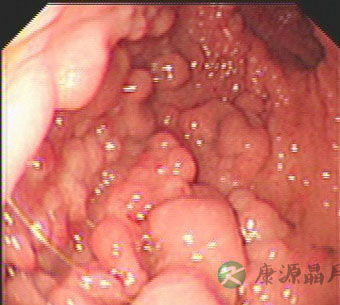

同一例胃息肉病患者的胃镜图片: